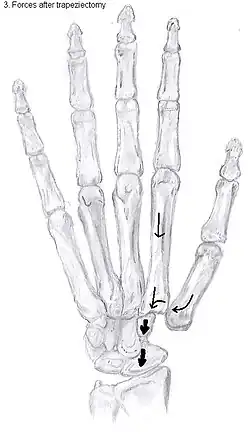

Trapeziectomy

During trapeziectomy,[30] the trapezium bone is removed without any further surgical adjustments. The trapezium bone is removed through an approximately three centimeter long incision along the lateral side of the thumb. To preserve surrounding structures, the trapezium bone is removed "by splitting" it into pieces.

An empty gap is left by the trapeziectomy and the wound is closed with sutures. Despite this gap, no significant changes in function of the thumb are reported.[27] After the surgery, the thumb will be immobilized with a cast.